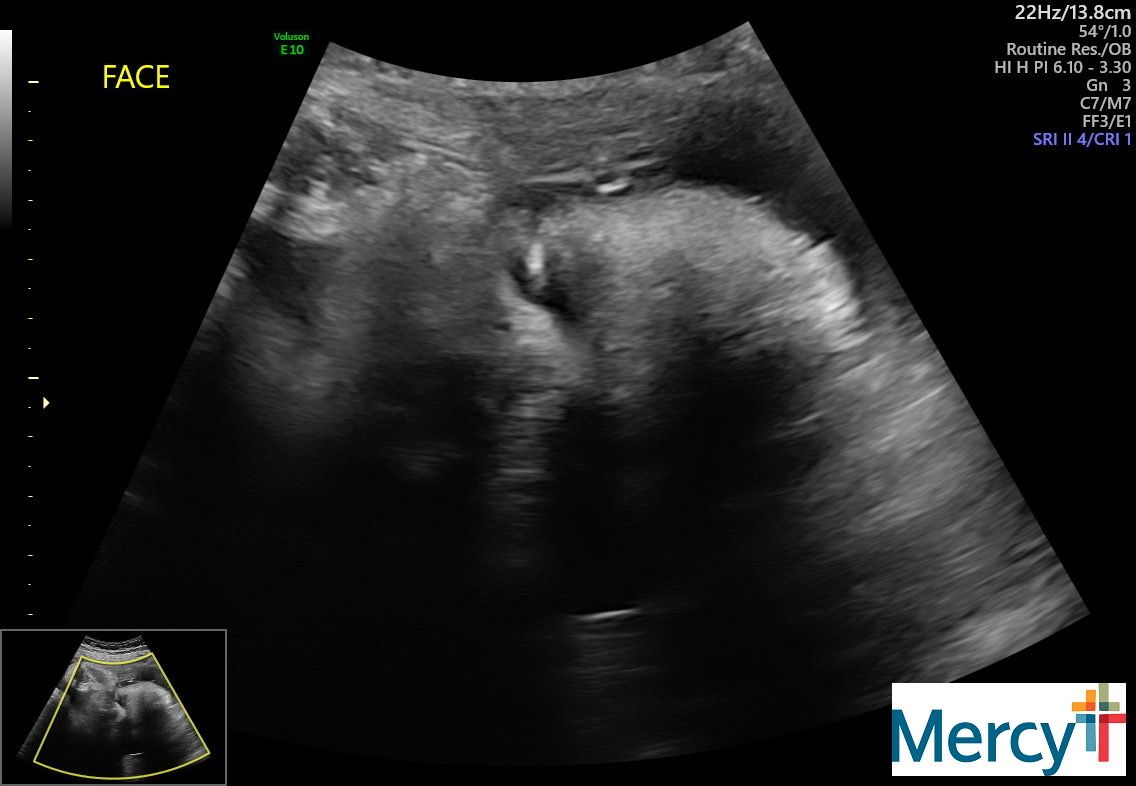

I am still going to the hospital twice a week to do a NST and an ultrasound for fluid levels. It's been pretty uneventful! The tech today told me he has a lot of hair. Yay!

Our final NST + ultrasound!!!